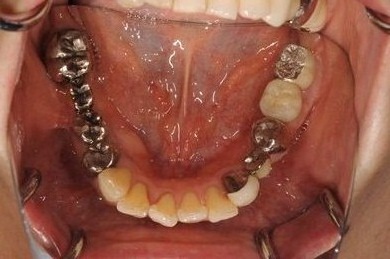

インプラントの症例写真 IMPLANT

インプラント治療+セラミック治療

| 性別/年齢 | 女性 / 52歳 | ||||||||||||||||||||||||||||||||

| 主訴 | 上の前歯の左側の1本が下がって来て歯ぐきに時々炎症がある。右側下の歯ぐきに時々炎症及び鈍痛がある。 | ||||||||||||||||||||||||||||||||

| 治療内容 | インプラント2本、オールセラミック4本(ジルコニアフレーム、オールセラミック用の土台1本) | ||||||||||||||||||||||||||||||||

| 総治療費 | 1,299,000円 | ||||||||||||||||||||||||||||||||

| 治療期間 | 7ヶ月 |